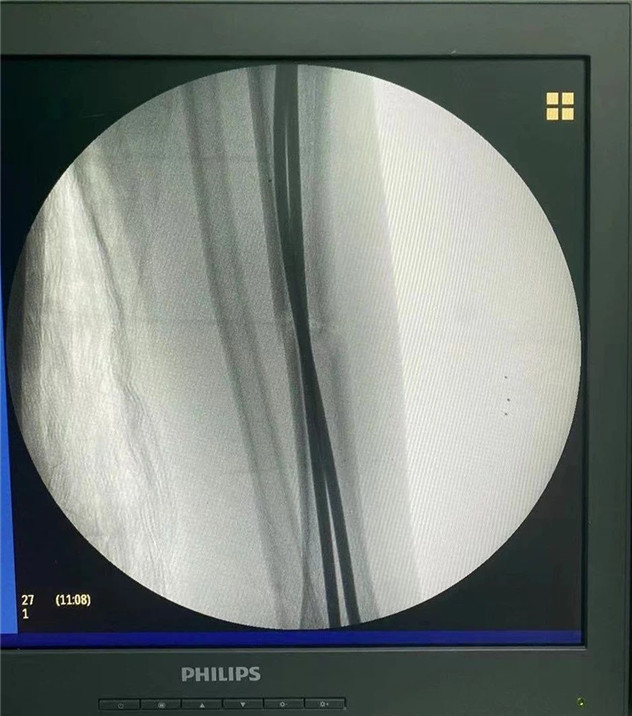

術(shù)中

2020年10月5日,在完成術(shù)前檢查后,睿睿接受了閉合復(fù)位彈性釘內(nèi)固定術(shù),手術(shù)由羅軍主任主刀。術(shù)中只需要兩個1厘米的小切口,精準(zhǔn)微創(chuàng),僅一個小時,手術(shù)便圓滿完成。